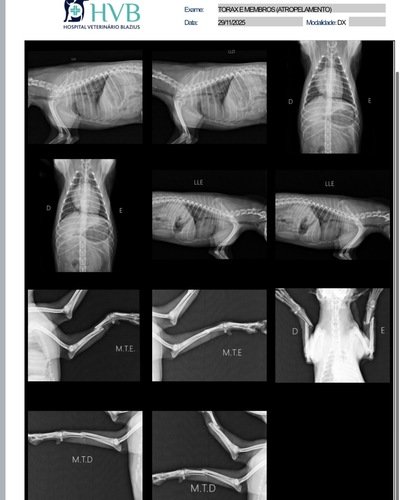

ele saiu na noite pra dar uma volta,como sempre costuma a fazer, mas não voltou, foi atropelado e quebrou as duas patinhas da frente, minha vizinha que encontrou e levou pro Hospital Veterinário Blazius, fizeram todos os raio x e exames e nos passaram o valor.